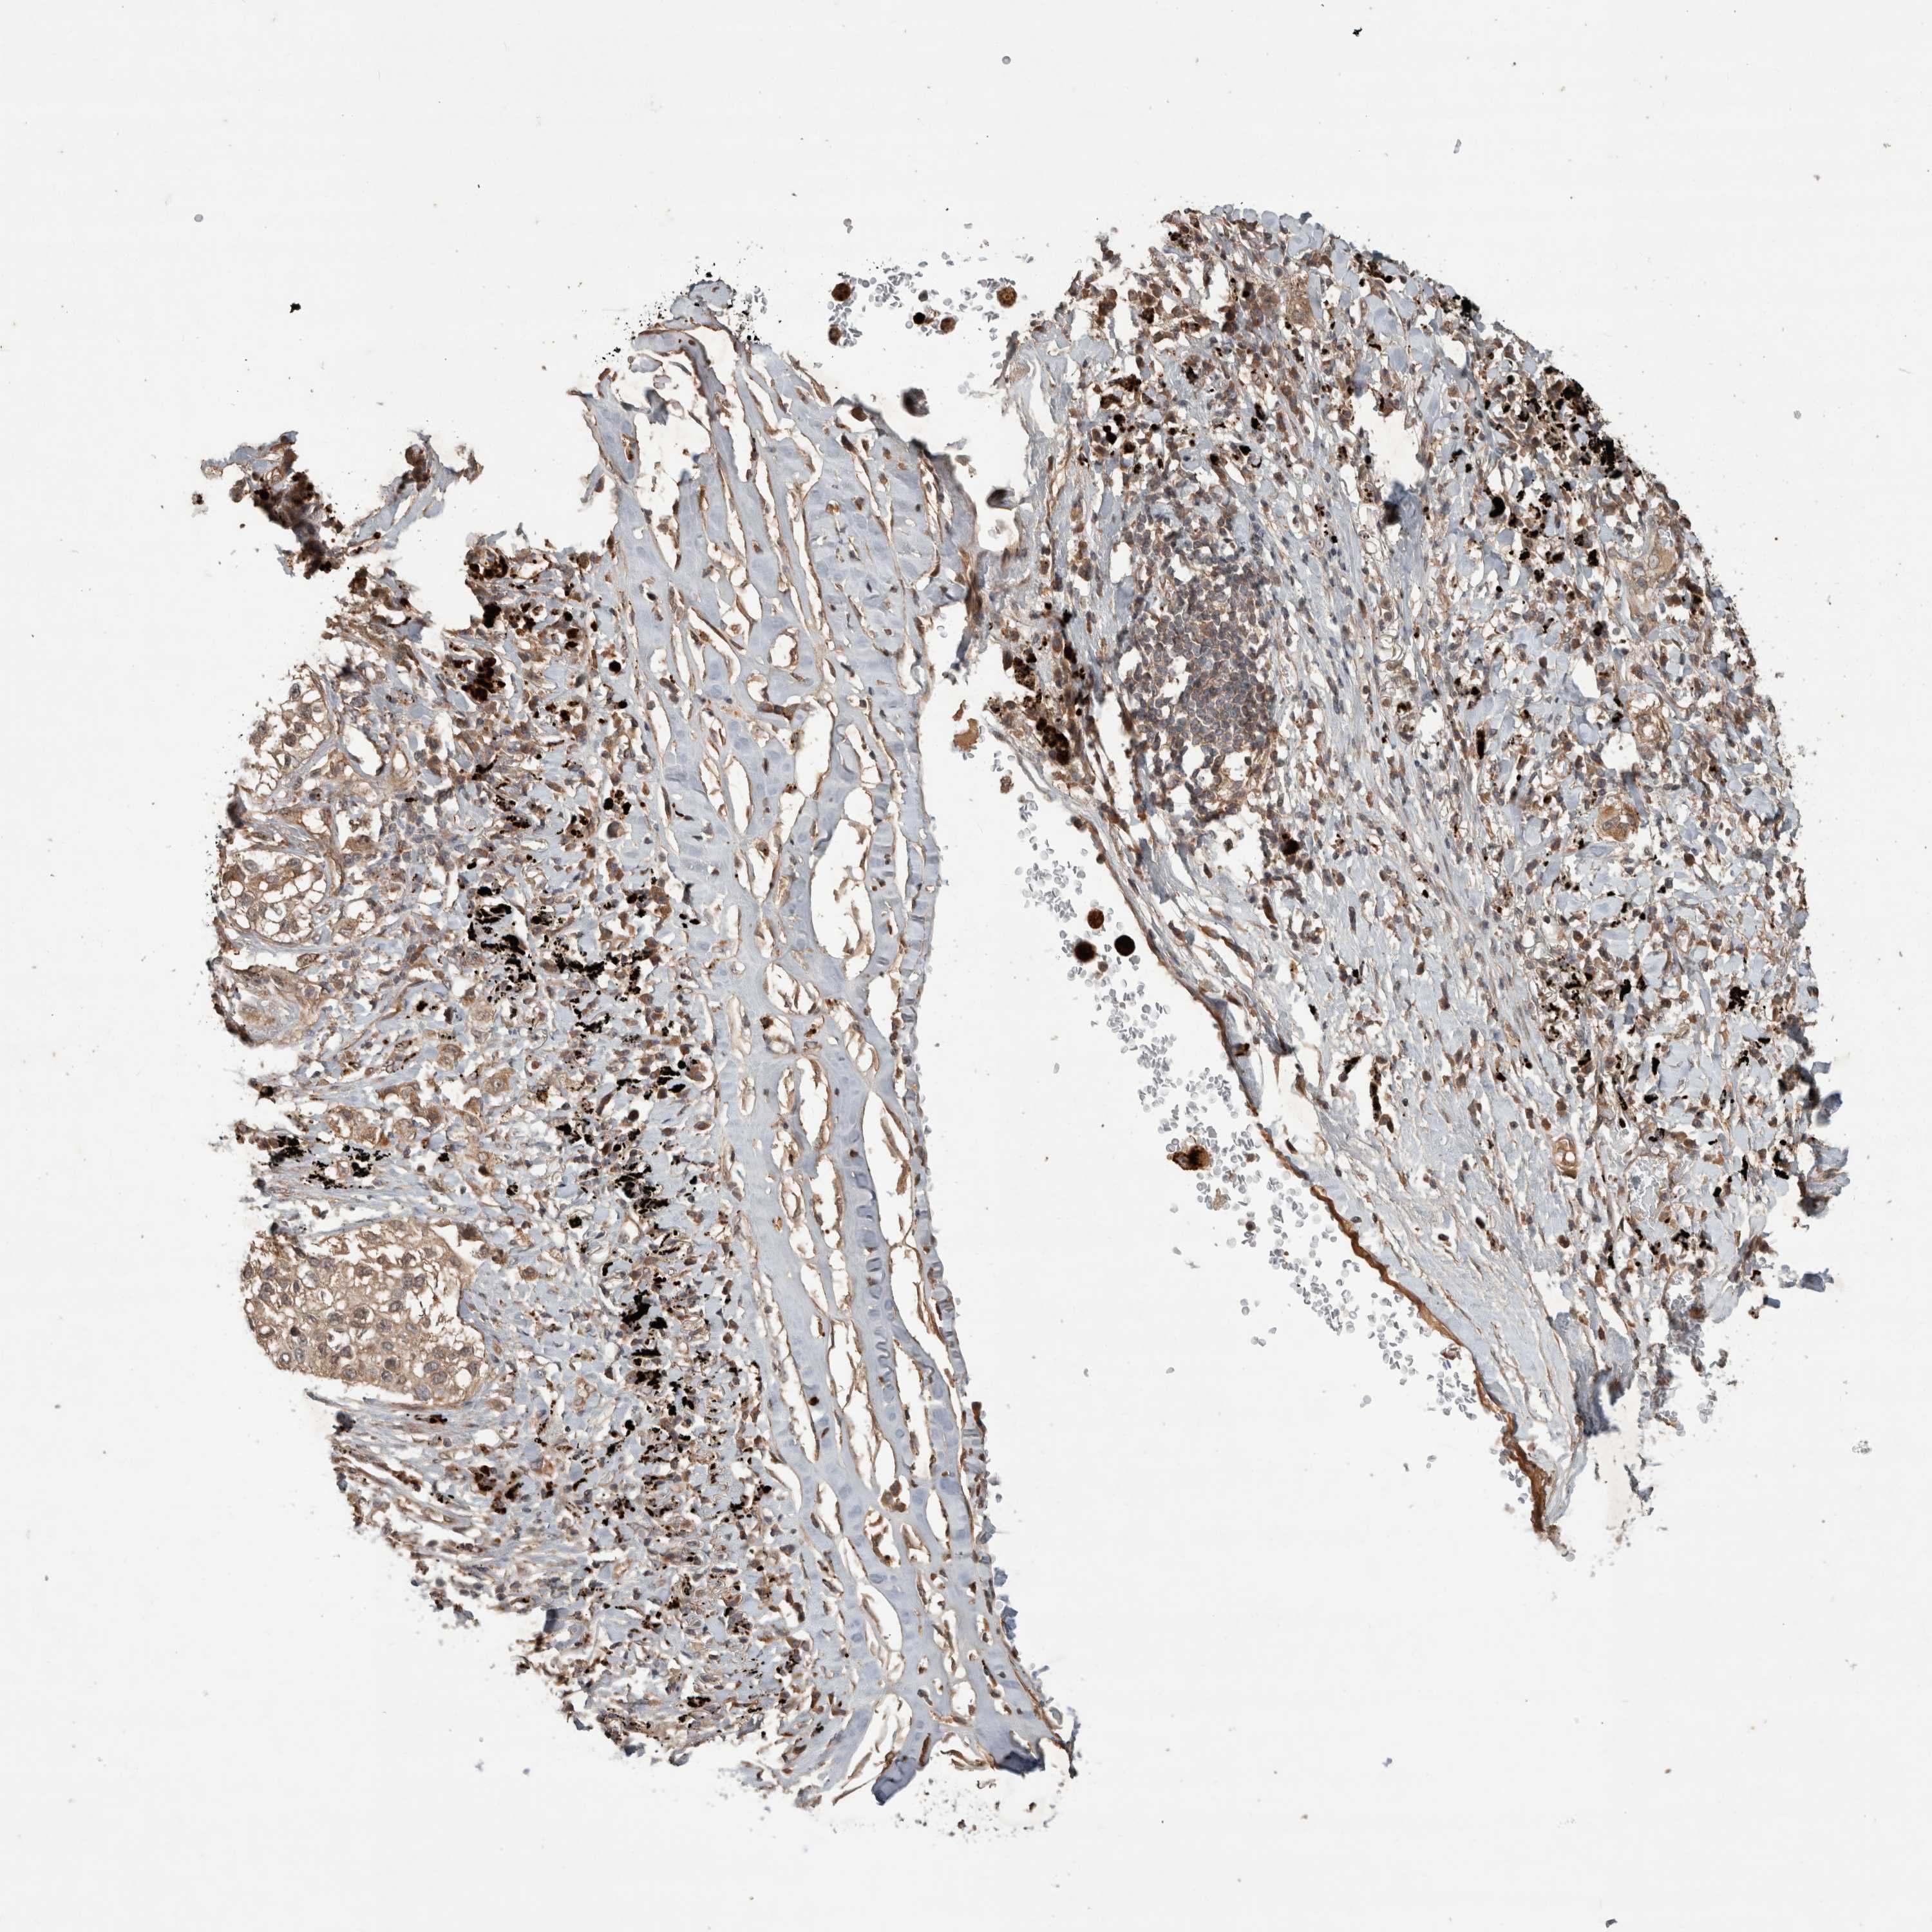

LUNG ADENOCARCINOMA (VALIDATION) - Interactive survival scatter ploti

The Survival Scatter plot shows the clinical status (i.e. dead or alive) for all individuals in the patient cohort, based on the same data that underlies the corresponding Kaplan-Meier plots. Patients that are alive at last time for follow-up are shown in blue and patients who have died during the study are shown in red.

The x-axis shows the expression levels (FPKM) of the investigated gene in the tumor tissue at the time of diagnosis. The y-axis shows the follow-up time after diagnosis (years). Both axes are complimented with kernel density curves demonstrating the data density over the axes. The top density plot shows the expression levels (FPKM) distribution among dead (red) and alive patients (blue). The right density plot shows the data density of the survived years of dead patients with high and low expression levels respectively, stratified using the cutoff indicated by the vertical dashed line through the Survival Scatter plot. This cutoff is automatically defined based on the FPKM cutoff that minimizes the p-score. The cutoff can be changed by dragging the vertical line or by entering a cutoff value in the square labeled "Current cut-off".

Under the Survival Scatter plot the p-score landscape (black curve; left axis) is shown together with dead median separation (red curve; right axis). Dead median separation is the difference in median mRNA expression between patients who have died with high and low expression, respectively. It is calculated as follows: median FPKM expression of dead patients with high expression - median FPKM expression of dead patients with low expression. This is intended to aid the user in visually exploring custom cutoffs and the associated p-scores and dead median separation.

Individual patient data is displayed and can be filtered by clicking on one or more of the category buttons on the top of the page. Categories describing expression level and patient information include: high, low, alive, dead, female, male and tumor stages. The scale of the x-axis can be toggled between linear and log-scale by clicking on the "x log" button. Mouse-over function shows TCGA ID, patient information and mRNA expression (FPKM) for each patient.

& Survival analysisi

Kaplan-Meier plots summarize results from analysis of correlation between mRNA expression level and patient survival. Patients were divided based on level of expression into one of the two groups "low" (under cut off) or "high" (over cut off). X-axis shows time for survival (years) and y-axis shows the probability of survival, where 1.0 corresponds to 100 percent.

PITPNC1 is not prognostic in Lung Adenocarcinoma (validation)

: 8.17

P scorei

N/A

Average pTPM 7.7

Number of samples 105